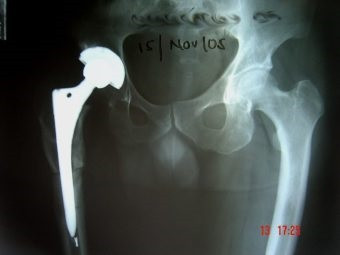

Prótesis Total de Cadera

Envíado por Dr. Ricardo Antonio Gómez G.